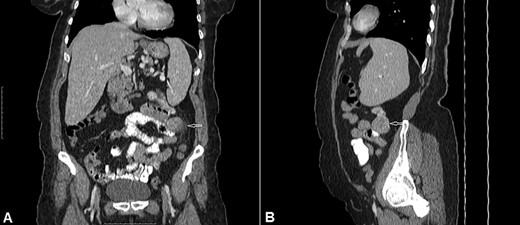

At laparotomy we found a hypervascular 4 × 3.5 cm mass in the proximal jejunum ~15 cm from the ligament of Treitz. The mass was protruding from the anti-mesenteric border and was of a very firm consistency. The small and large bowel was seen to be loaded with blood (Fig. 3). As per the CT scan there was no sign of any intraperitoneal metastases or enlarged lymph nodes. The mass was resected with a margin of 4 cm on either side and a primary anastomosis performed. The postoperative course was uneventful and she was discharged on Day 7 post op.

Intraoperative view: hypervascular 4 × 3.5 cm extraluminal mass of proximal jejunum. Small and large bowel are loaded with blood.